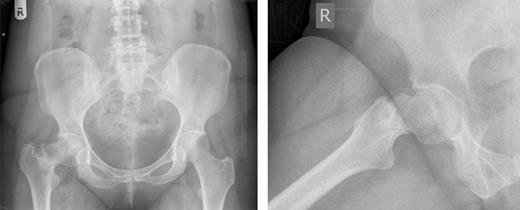

Pelvic and right hip radiograph's taken 5 months after the onset of symptoms demonstrating the fracture neck of femur.

A 39-year-old office worker presented to the fracture clinic with 5 months of right groin pain and difficulty in mobilization. She reported spontaneous, acute onset of pain with little improvement with analgesia and sufficient intensity to prevent weight-bearing. Six months prior to the onset of symptoms, she recalled slipping on a wet floor. However, she did not have pain until 6 months later and had not associated this event with her current problems. She was previously fit and active taking only a contraceptive pill as regular medication. She had no risk factors for stress fractures. Prior to review in the fracture clinic, she consulted a number of health-care professionals on multiple occasions. She was initially diagnosed with sciatica and given analgesia and physiotherapy. With little improvement in her symptoms and repeated visits to the emergency department and her general practitioner, she was suspected to have trochanteric bursitis and given a steroid injection and further physiotherapy. Throughout this period her symptoms remained unchanged and she required a stick for mobilization. Five months later, an X-ray was finally requested revealing a fracture and prompting referral to the fracture clinic.